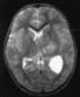

Teratoid tumor

An atypical teratoid rhabdoid tumor (AT/RT) is a rare tumor usually diagnosed in childhood. Although usually a brain tumor, AT/RT can occur anywhere in the central nervous system (CNS), including the spinal cord. [Source: Wikipedia ]